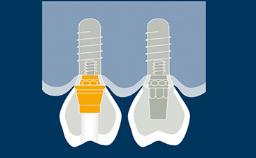

Um pilar de implante é a parte ou componente que serve como suporte e/ou retenção para uma prótese dentária. A seleção do pilar do implante para cada paciente é, portanto, uma parte importante da fase de tratamento com implante-prótese. Neste módulo, discutiremos a função dos pilares de implantes, diferentes tipos de pilares para implantes, diferentes materiais de pilares e como selecionar um pilar com base em um processo determinado pela prótese.

- definir a função de um pilar de implante

- selecionar pilares baseados em indicações protéticas e planejamento